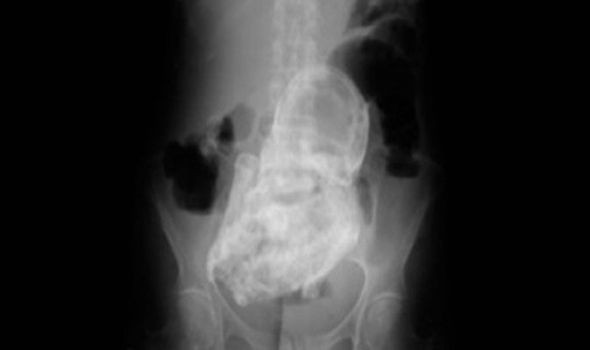

Milliyet gazetesinin haberine göre, X-Ray cihazında yapılan muayene sonucu ortaya çıkan taşlaşmış bebeğin kolları ve ayaklarını bile belirgin şekilde görmek mümkün.